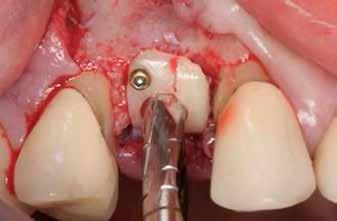

A fogak eltávolítása minimálinvazív módon történt, amelynek során a parodontális rostokat egy periotom segítségével átvágtuk, így lebenyes feltárásra nem volt szükség (3. a–b ábrák) . Az implantátumokat a frissen eltávolított fogak alveolusaiba ültettük be. A foghúzást követően minden alveolust alaposan ellenőriztünk az endodontiai, vagy parodontális eredetű gyulladásos szövetmaradványok eltávolítása érdekében, majd fiziológiás sóoldattal bőségesen átöblítettük. Megfelelő előfúrást követően a kerámiaimplantátumokat 30 fordulat/perc sebességgel és 35 Ncm behajtási nyomatékkal helyeztük be (4. a–b ábrák) . A réseket csontpótlóval töltöttük ki (Maxresorb ® 0,5–1,0 mm szemcseméret, 0,5 cm 3 térfogat, Straumann ®; 6. ábra ).

Azonnali ideiglenes fogpótlás

A műtétet követően önkötő akrilátból ideiglenes koronákat készítettünk, amelyeket cementtel rögzítettünk a cirkónium-dioxid ideiglenes fejeken (CR Zi Pillar®, 7. a–c ábrák ).